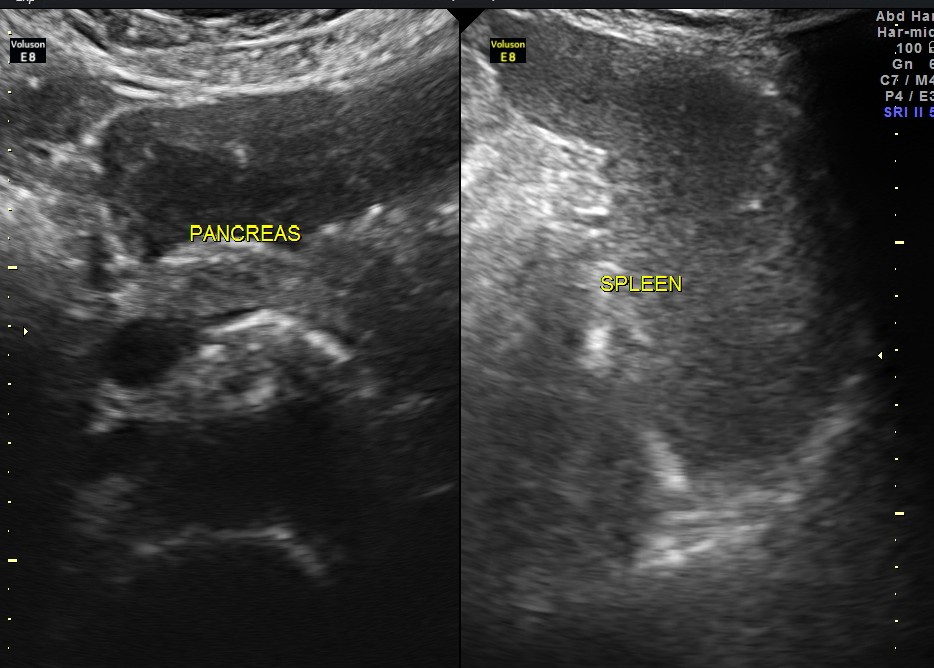

The diagnosis offered was multiple liver secondaries with incidental finding of shrunk right kidney with probable reduced function.